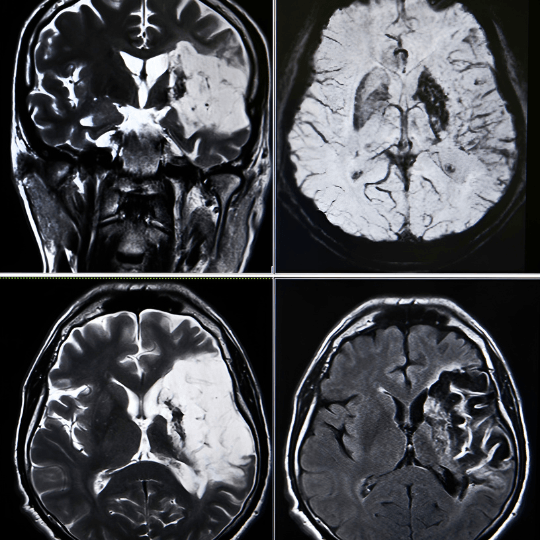

Existem dois tipos principais de AVC: o isquêmico, causado por um bloqueio em uma artéria que impede o sangue de chegar ao cérebro, e o hemorrágico, que acontece quando um vaso sanguíneo no cérebro se rompe, causando sangramento na área afetada.

Ambos os tipos podem levar a danos cerebrais graves, comprometendo funções como movimento, fala, visão e memória. Os sintomas comuns incluem fraqueza em um lado do corpo, dificuldade em falar, perda de equilíbrio e confusão mental.